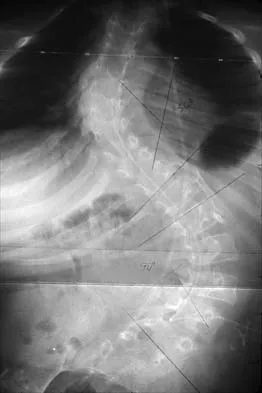

A 50-year-old man with no history of trauma reports new-onset back pain after doing some yard work the previous day. He reports pain radiating down his leg posteriorly and into the first dorsal web space of his foot. MRI scans are shown in Figures 3a through 3c. What nerve root is affected?

Detailed Explanation